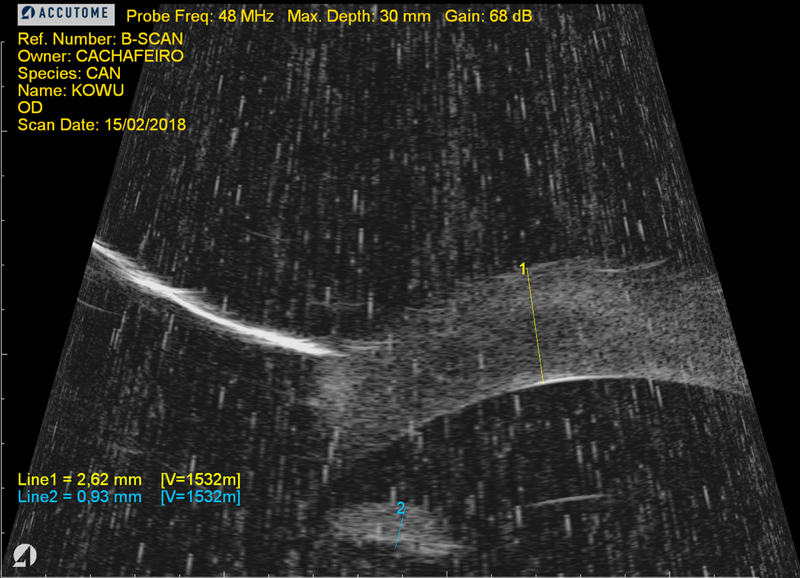

- Ecografia ocular

- Ojo derecho: ulcera estromal profunda con queratomalacia (opacidad de la córnea).

- Se observó un espesor corneal disminuido en la zona de ulceración mas profunda con presencia de colagenolisis.